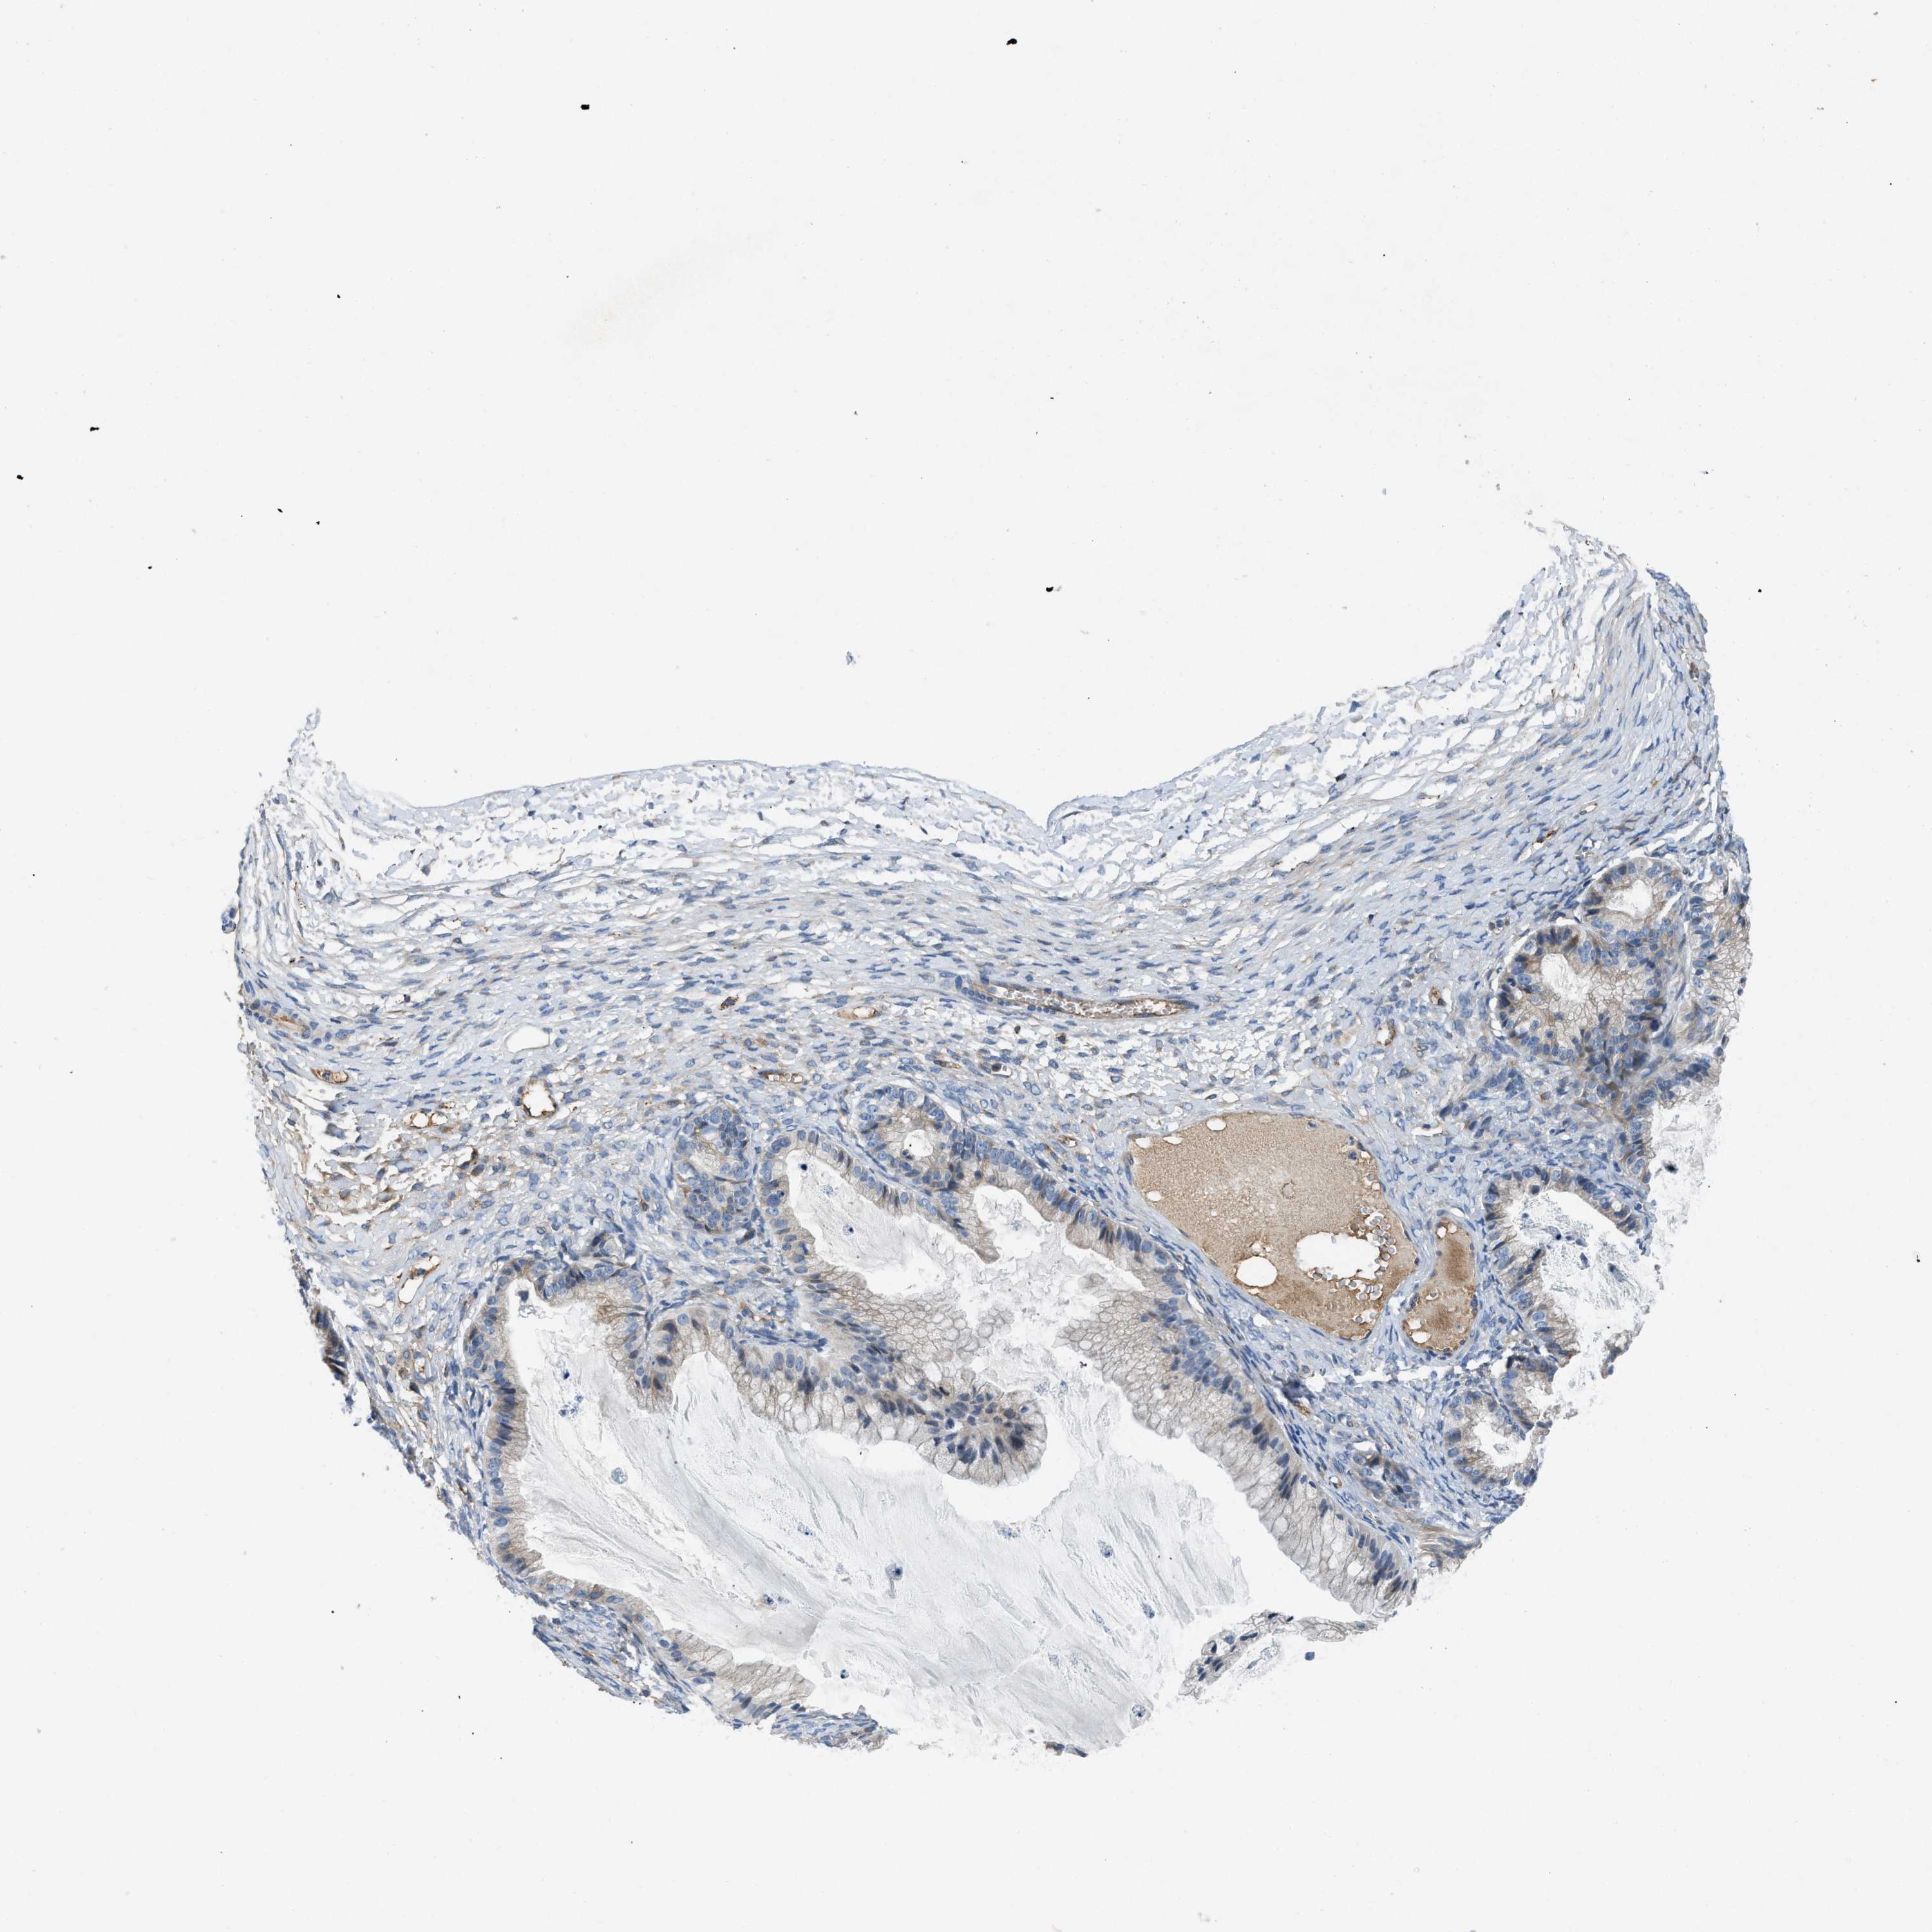

OVARIAN CANCER - Protein expressioni

A mouse-over function shows sample information and annotation data. Click on an image to view it in a full screen mode. Samples can be filtered based on level of antibody staining by selecting one or several of the following categories: high, medium, low and not detected. The assay and annotation is described here.

Note that samples used for immunohistochemistry by the Human Protein Atlas do not correspond to samples in the TCGA dataset.

Antibody stainingi

Antibody staining in the annotated cell types in the current human tissue is reported as not detected, low, medium, or high, based on conventional immunohistochemistry profiling in selected tissues. This score is based on the combination of the staining intensity and fraction of stained cells.

Each image is clickable and will lead to virtual microscopy that enables deeper exploration of all samples and also displays staining intensity scores, fraction scores and subcellular localization as well as patient and tissue information for each sample.

Antibody HPA018284

Staining

High

Medium

Low

Not detected

Intensity

Strong

Moderate

Weak

Negative

Quantity

>75%

75%-25%

<25%

None

Location

Nuclear

Cytoplasmic/membranous

Cytoplasmic/membranous,nuclear

Cystadenocarcinoma, serous, NOS

Carcinoma, endometroid

Cystadenocarcinoma, mucinous, NOS

Carcinoma, NOS